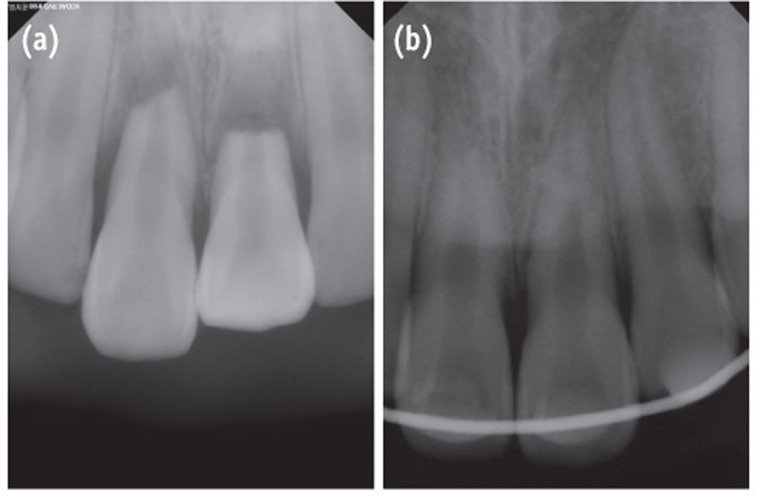

Case 3

A 13-year-old female patient was referred to the Department of Conservative Dentistry at the Wonkwang University Dental Hospital (Iksan, Korea) for the evaluation of her maxillary anterior teeth. Seven days previously, the maxillary central incisors were traumatized when she slipped on the stairs and fell down. The coronal fragments of the incisors were luxated laterally, thereby showing the exposed labial surface of the root. The patient's medical history was noncontributory. The emergency dentist diagnosed the teeth as having horizontal root fractures with alveolar bone fractures. The teeth were repositioned with a rigid splint (Figure 4).

One week after the trauma, both teeth had a normal response to pulp vitality tests. Three weeks later, localized swelling was observed on the labial gingiva of the maxillary left central incisor, and a radiolucent lesion was present near the fracture line. Both teeth had no responses to the thermal and electronic pulp tests. The narrow and deep pocket (approximately 8 mm) were explored by a dental probe through the gingival sulcus to the swollen portion (Figure 5). Root canal treatment was initiated on both coronal fragments of the teeth with K-file and irrigated with 5% sodium hypochlorite. Working length was established with an apex locator (DentaPort ZX). Calcium hydroxide was applied into the canals between appointments. The deep pocket was debrided because of the possibility of the insertion of a foreign body at the time of the accident. At the 2-month follow-up evaluation, the swelling had disappeared and pocket depth was reduced to 3 mm. The canals were obturated with MTA (ProRoot) confined to the coronal fragment (Figure 6a).

At the 6-month and 1-year follow-up evaluation, she did not complain of any pain. However, she reported occasional swelling of the gingiva of the maxillary left central incisor. Clinically normal probing depth and normal response to percussion were observed on the teeth. Radiographic examination showed that the radiolucent area near the fracture line of the maxillary left central incisor had decreased, but the lesion remained (Figure 6b). At the 1½-year evaluation, a fragment of tooth-like material was observed in the gingival swelling area and the fragment was removed. At the 2-year follow-up evaluation, she reported no recurrence of gingival swelling since her last visit to the dental hospital. Slight mobility remained, but both teeth were retained well in the maxillary arch without any discomfort. Radiographic examination showed the teeth were healed with soft tissue between the fragments (Figure 6c).

In Case 3, a fragment of tooth-like material was observed on the gingival swelling area at 18 months after the trauma. After removing the fragment, gingival swelling disappeared and radiolucency around the fracture line was decreased, which indicated periodontal healing. Residual infected material can cause a persistent or new radiolucency, thereby interfering with the healing of periodontal tissue.1,3 A foreign body may act as an inflammatory source in the space between fragments.

Andreasen and Hjorting-Hansen classified the healing of root-fractured teeth into four groups, (1) healing with hard tissue, (2) healing with the interposition of hard and soft tissue, (3) healing with interposition of soft tissue, and (4) no healing.12 The factors influencing the healing of a root-fractured tooth include the patient's age, stage of root growth, mobility of the coronal fragment, and diastasis of the fragments.1 In the present patients, injury factors (e.g., fragment diastasis and mobility of the coronal fragment) exerted a strong influence on healing at the fracture line and on pulpal necrosis. Case 1 had small diastasis of less than 0.5 mm and no mobility, and the tooth healed with hard tissue and with the evidence of a spontaneous healing process such as ISR. Case 2 showed extrusive luxation of the crown fragment with a large amount of diastases. It was impossible to determine whether the pulp was vital because root canal treatment had been already initiated by the emergency dentist. The follow-up radiographs showed healing with hard and soft tissue. Case 3 showed lateral luxation of the crown fragment with a large amount of diastases. Interposition of soft tissue with pulp necrosis of coronal fragment was also observed. Increasing diastases between fragments reportedly increases the risk of pulp necrosis, and decreases the likelihood of hard tissue healing.13 According to a report, the frequency of pulp necrosis is stable with diastasis of up to 1 mm, whereas hard tissue healing shows stable values up to 0.5 mm.13

Figure 4

Radiographs of the emergency visit shows the teeth. (a) Before the application of the resin-wire splint; (b) After repositioning and the application of the resin-wire splint.

Figure 5

Images were obtained 3 weeks after the trauma. (a) The periapical radiograph shows a radiolucent lesion around the fracture line on tooth #21; (b) The clinical photograph shows narrow and deep pocket depth and gingival swelling on tooth #21.

Figure 6

Radiograph of the teeth. (a) After the root canal treatment; (b) At the 1-year follow-up evaluation; (c) at the 2-year follow-up evaluation. The radiolucent lesion has disappeared on tooth #21. 2-year follow-up radiograph reveals healing with interposition of soft tissue between the fragments.